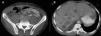

En la tomografía axial computarizada toracoabdominal (fig. 1B) se apreciaban infiltrados pulmonares parenquimatosos, más evidentes en el lóbulo medio, que se extendían hasta la pleura. En el abdomen, el hígado tenía múltiples lesiones ocupantes de espacio (fig. 2A) y en la estructura ósea se observaban lesiones líticas indicativas de metástasis en columna dorsolumbar, esqueleto pélvico, ramas isquiopubianas y acetábulo (fig. 2B).

Fig. 2. Tomografía axial computarizada de abdomen (A), donde se objetivan múltiples metástasis hepáticas bilaterales, y pélvica (B), donde se aprecian metástasis óseas líticas en pelvis y cuerpo vertebral.